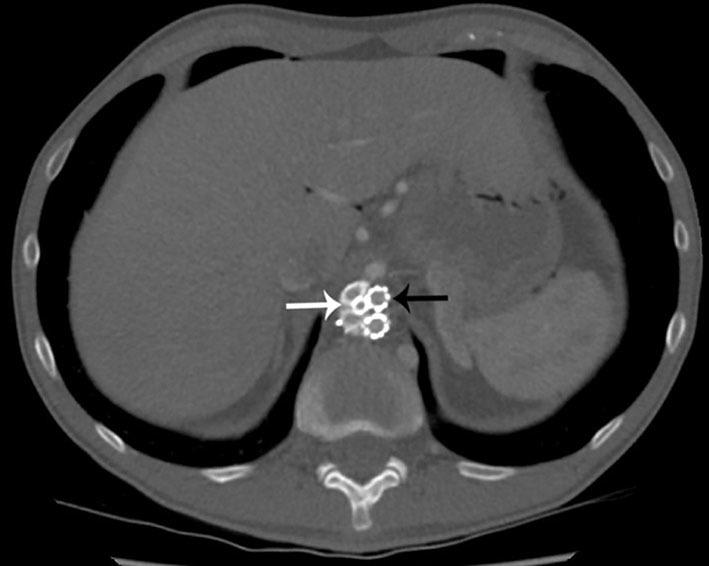

The Nellix endovascular aneurysm sealing system is a relatively new aortic endoprosthesis designed to overcome the problems associated with traditional methods of endovascular aneurysm repair. We report a case in which a 65-year-old male with abdominal pain was mistakenly diagnosed with an acute aortic dissection 7 days postoperatively after Nellix stent insertion, on the basis of the CT angiography findings. This report highlights the typical radiological appearances of the Nellix stent.

内利克斯血管内动脉瘤封堵系统是一种相对较新的主动脉内假体,旨在克服与传统血管内动脉瘤修复方法相关的问题。我们报告了一例病例,一名65岁男性在植入内利克斯支架术后7天因腹痛被误诊为急性主动脉夹层,诊断依据是CT血管造影结果。本报告重点介绍了内利克斯支架的典型影像学表现。